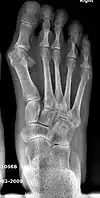

Primus varus deformity

Primus varus deformity is the leaning of the first metatarsal bone away from the second metatarsal and towards the opposite foot (Fig. 1). As it leans over, its head sticks out to form the bunion bump and it also widens the forefoot to cause shoes feeling too tight. Thus when bunion pain becomes unmanageable, surgical correction is to narrow the forefoot by repositioning of the first metatarsal head back to its normal position. This can be done by osteotomy (bone-breaking), soft tissue (non-osteotomy) or fusion techniques.